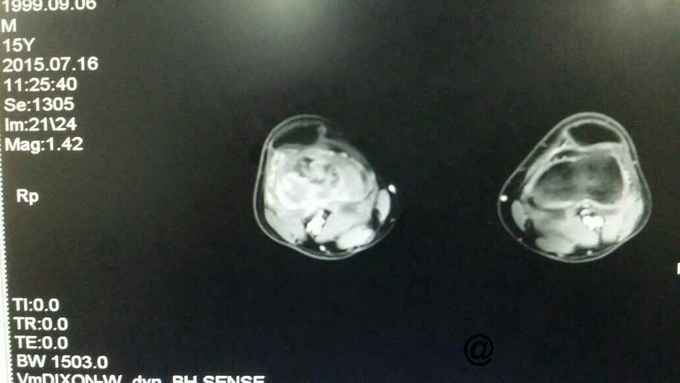

完善术前各项检查,检验,穿刺活检回示:考虑骨肉瘤,参加省病理会诊及北京积水潭会诊回示:符合骨肉瘤,进行术前新辅助化疗,期间定制肿瘤假体,化疗2个周期后,患者复查磁共振,肿块明显缩小,行右股骨远端骨肉瘤肿瘤膝关节置换术。

随访:患者术后化疗4个周期,现患肢功能锻炼良好。 讨论:肿瘤膝关节置换,要求首先明确病例诊断,术前新辅助化疗,术中广泛切除病变组织,包括穿刺点周围组织,术后辅助化疗。